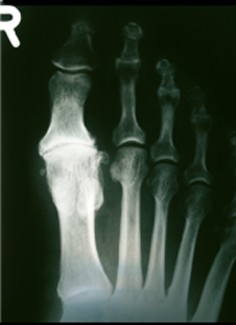

Radiografia di alluce rigido

Alluce ridido

- Artrosi deformante

- Riduzione della cartilagine

- Diminuzione della flessione dorsale

- Sovraccarico funzionale dell'alluce